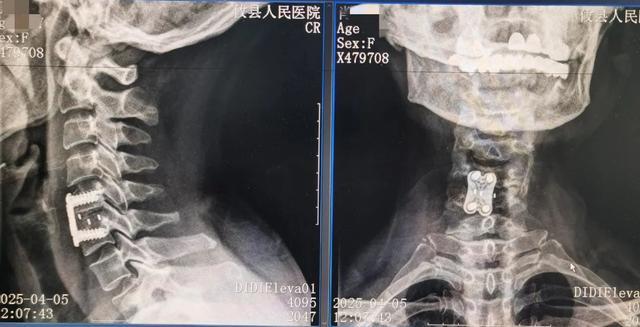

在攸县人民医院,肖女士受到了骨一科专业团队的热情接待。医生为她进行了详细的术前检查,通过颈椎X线、CT和MRI等影像学检查,全面评估她的颈椎状况。

随后,在科主任易爱江的带领下,共同为肖女士制定了个性化的手术方案,并成功实施了ACDF手术。

ACDF,即颈椎前路椎间盘切除融合术,是一种颈椎病的经典微创术式。简单来说,就是通过切除突出的颈椎间盘和增生的骨质,解除对脊髓或神经根的压迫,从而缓解患者的症状。

手术过程中,医生会在颈椎前方做一个3~4厘米的小切口,通过肌肉间隙入路,突破传统手术“层层剥离”的局限,达到手术区域。这种微创技术不仅创伤小、出血少,而且术后康复快,能够大大减少患者的痛苦。